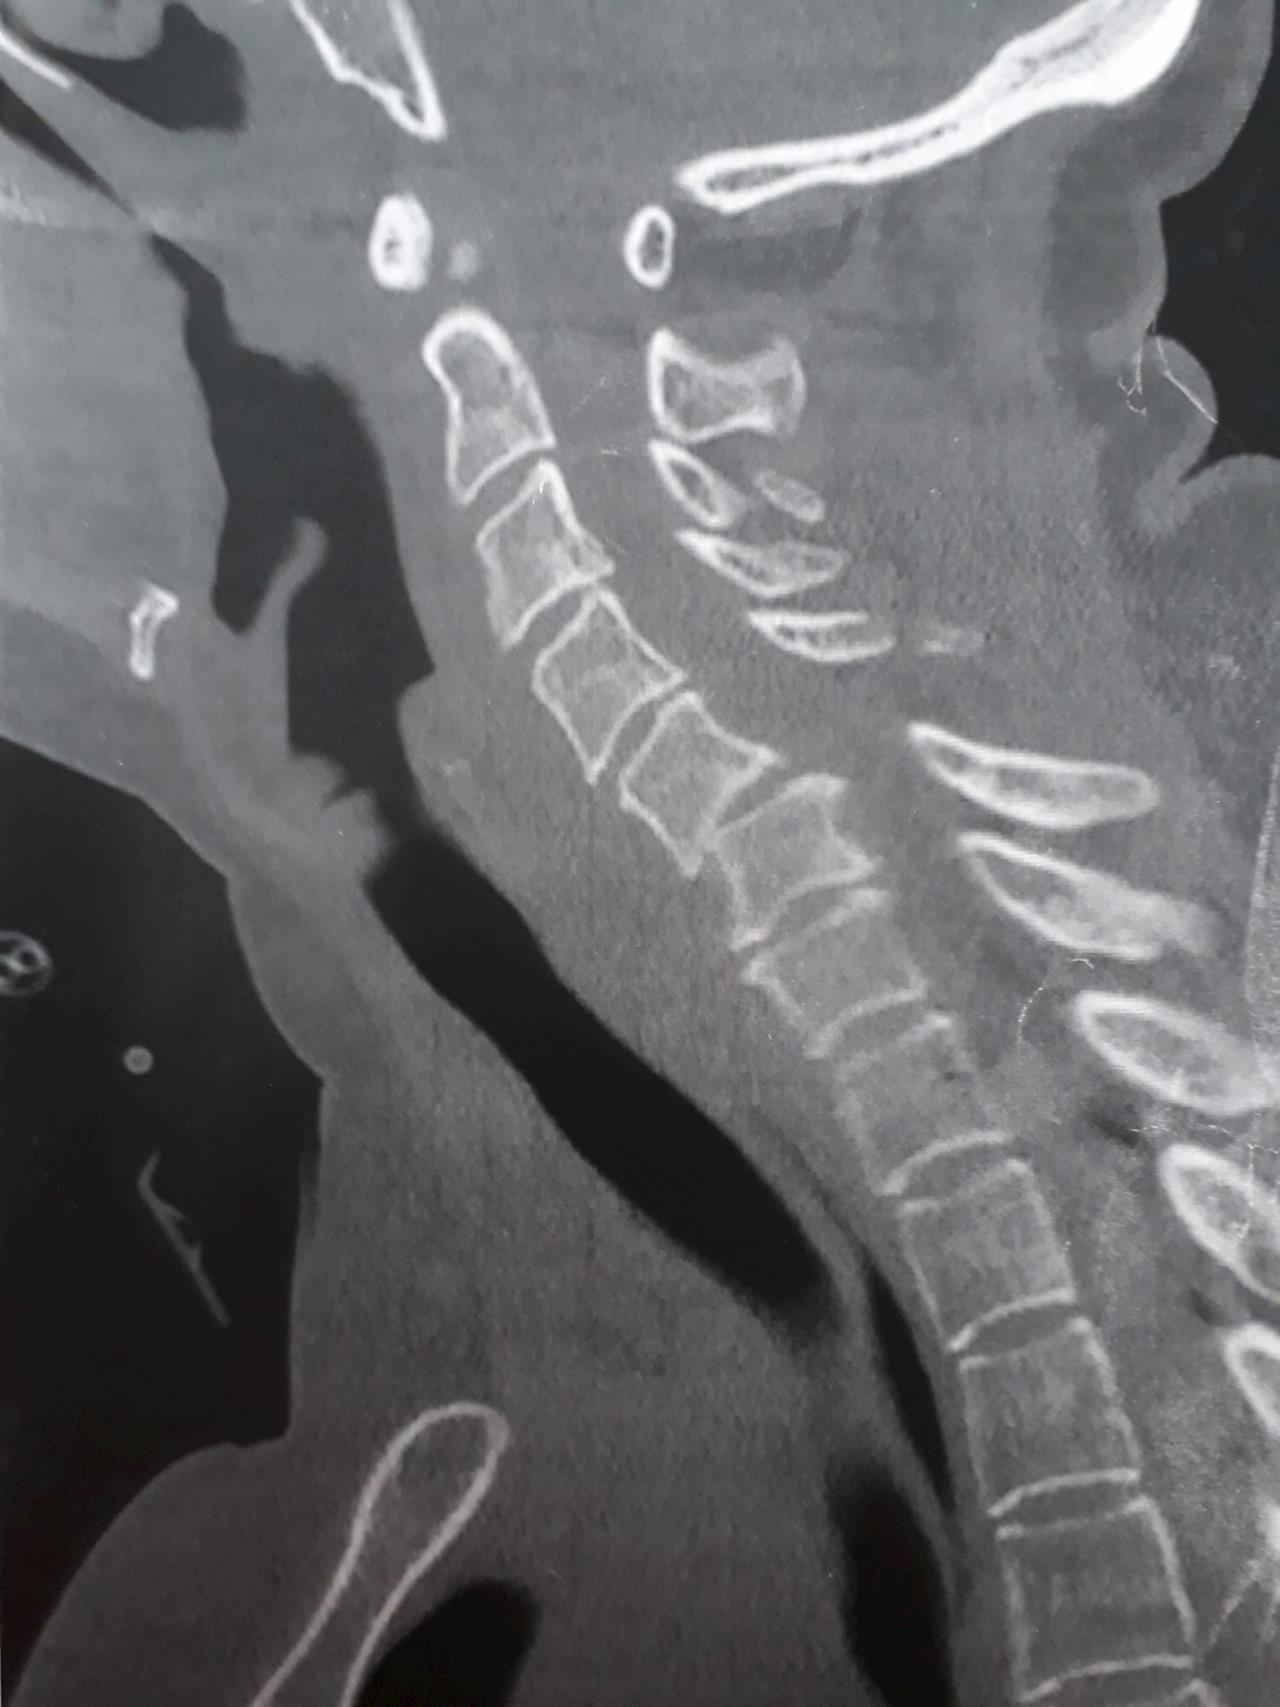

Main image

First a big thanks goes out to the team of social workers, doctors, nurses, OT and physios who are taking great care of Mum and keeping us up to date. Today we found out ACC has approved Mums claim, a real blessing. The doctors informed us Mums injury is @ C 5-6, A (B) on the ASIA Impairment Scale from C4 = some sensory and motor preservation but it is more than likely Mum will never walk again but have some limited motor function in her arms and hands, BUT our God can raise the dead ! Please pray that our God will continue to give us all peace, strength and hope. Mums is holding up well overall but being so dependent on other would leave any of us feeling vulnerable and anxious, territory no one likes to travel. Lots of new things to learn and tears to shed as waves of this new reality set in, I am confident tho that God will continue to reveal himself among the mess and turn a crappy situation into a blessing .. in time. Blessings J and the Family